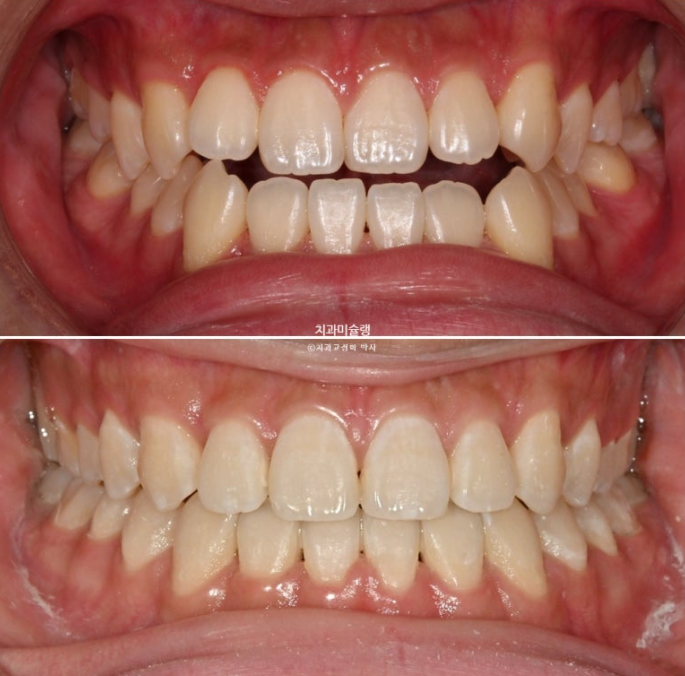

중심선은 정확히 맞으며 개방교합은 충분히 해소되었습니다.

반대교합은 개선되었고 교합관계는 1급을 달성

이제 전후 비교 보겠습니다.

치료 도중 군입대를 하면서 치료가 지연되어 토탈 기간은 2년 6개월 걸렸습니다.

23.06~26.01